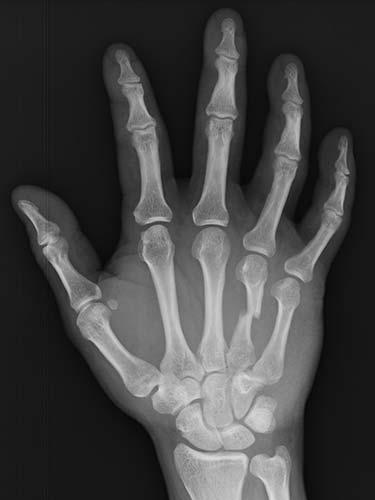

31 year old that suffered a broken bone in his hand while at work. Attempts were not possible at treating the patient without surgery because of the need to use his hand to help out with family obligations. He chose to have the hand treated with temporary wires that allowed him to help out with family obligations. The patient healed without any problems having regained full use of his hand.

- Before